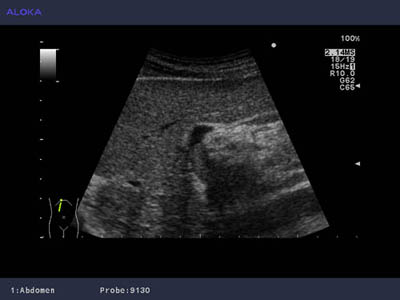

Ultrasound image of hepatocellular carcinoma